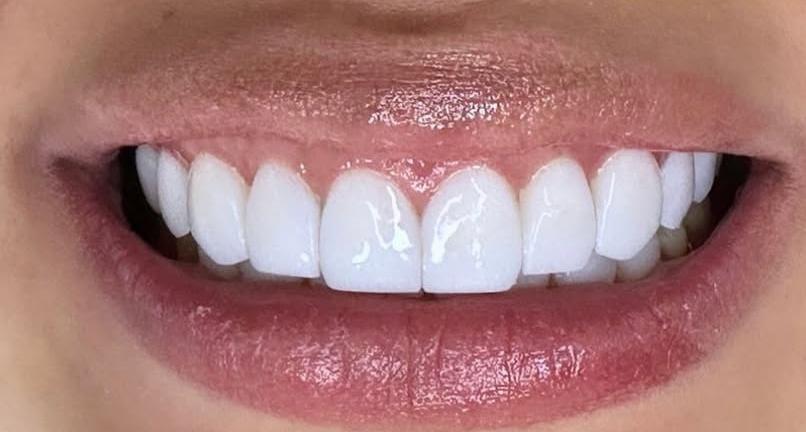

Es un procedimiento quirúrgico dental que consiste en la remoción de una parte del tejido gingival (encía). Se realiza principalmente por dos razones:

1. Estética: Para mejorar la apariencia de la sonrisa, por ejemplo, en casos de “sonrisa gingival” donde se muestra mucha encía al sonreír.

2. Terapéutica: Para tratar enfermedades periodontales, eliminando tejido afectado por inflamación crónica, permitiendo una mejor limpieza de las bolsas periodontales.